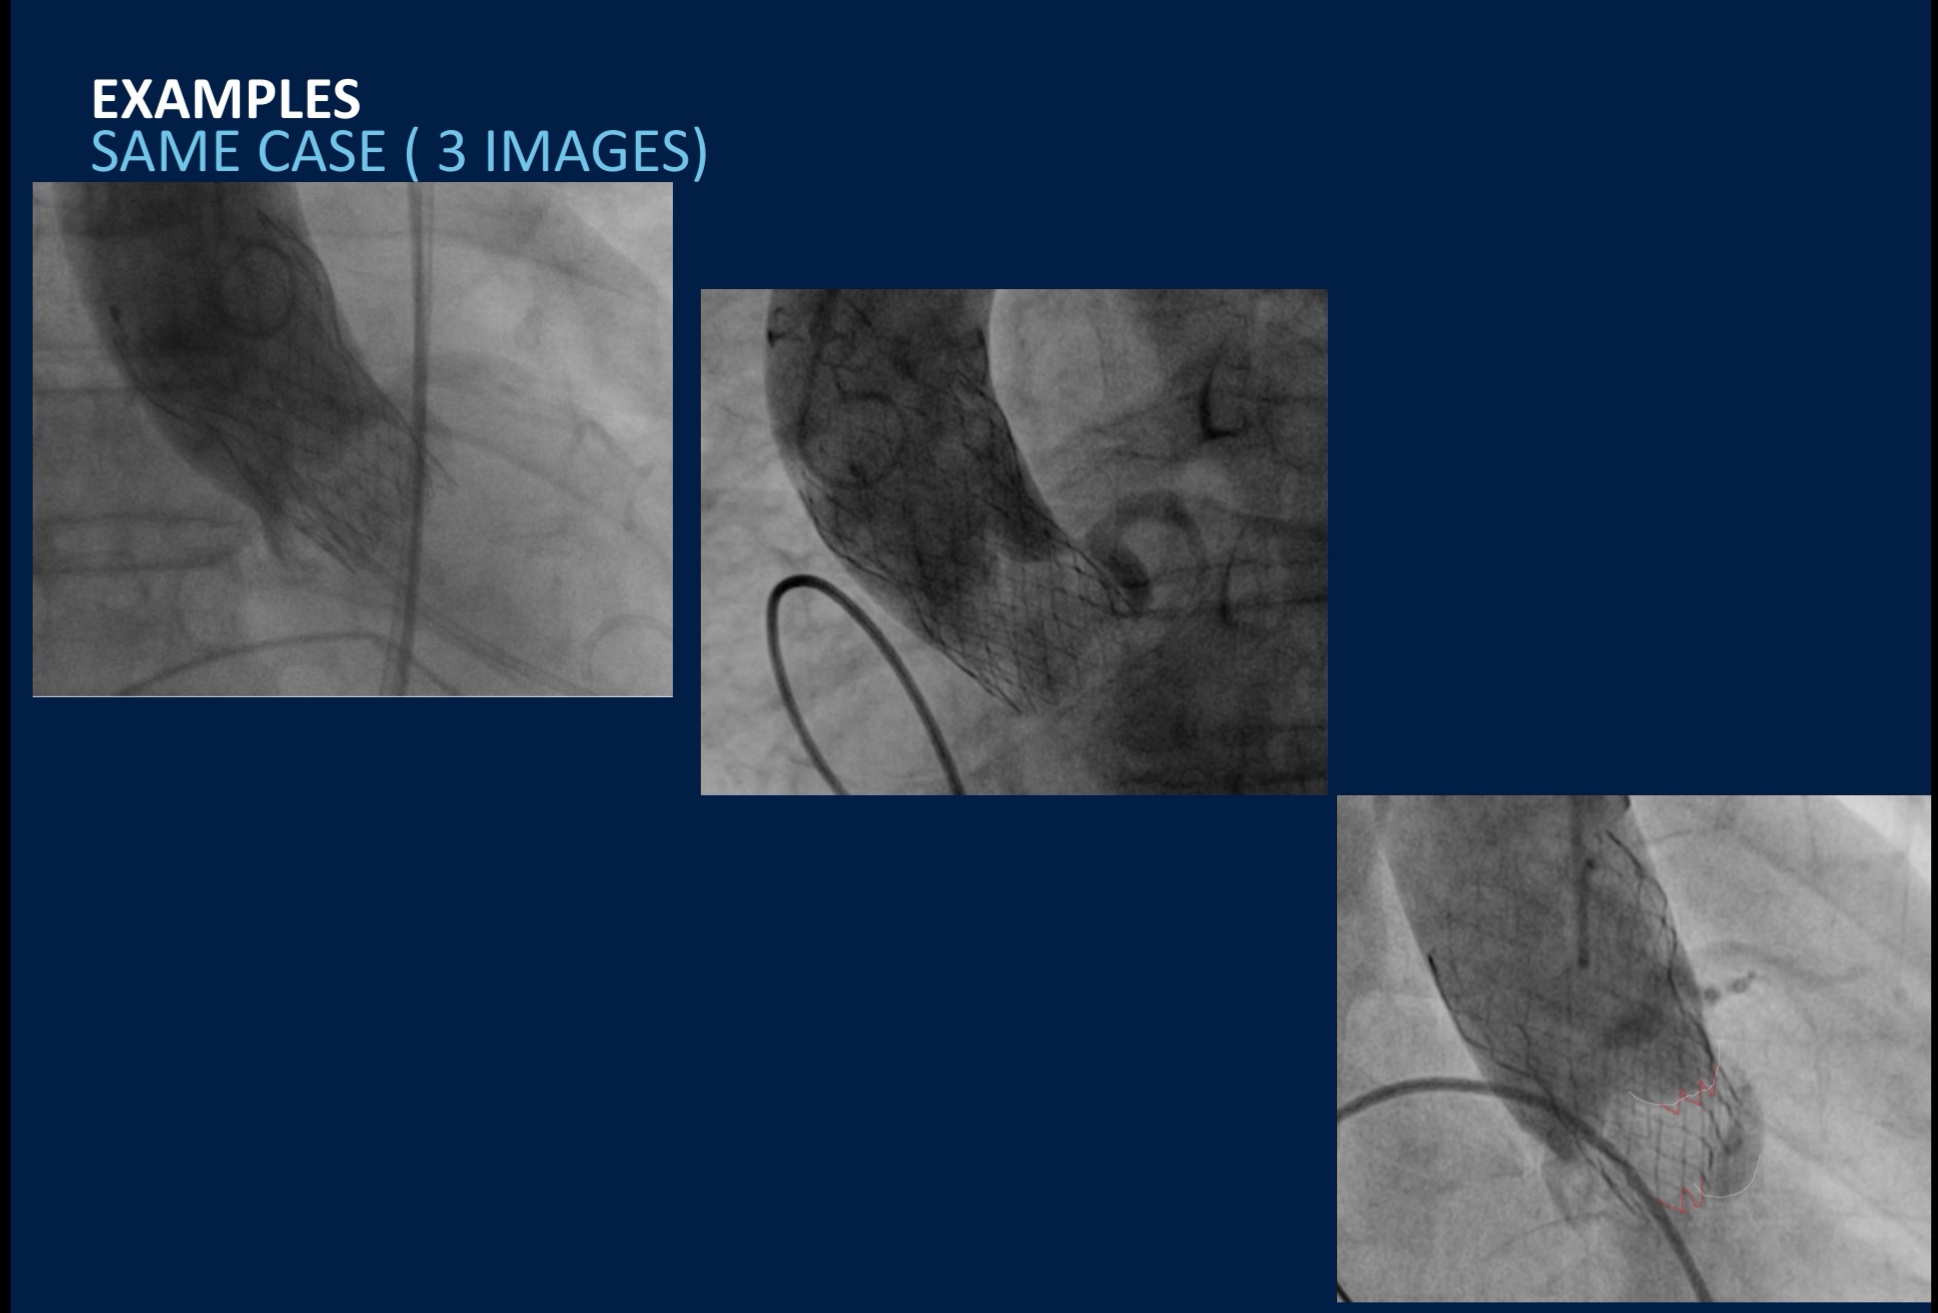

Esso può essere eseguito “a cuore aperto” oppure con la TAVI (Transcatheter Aortic Valve Implantation).

L’impianto percutaneo della valvola aortica (TAVI) può essere considerato come un’alternativa all’intervento di sostituzione valvolare chirurgico tradizionale in caso di controindicazione e/o alto rischio chirurgico se tale approccio è di pari efficacia clinica e presenta un rischio più basso

Dal maggio 2016, dopo relativa certificazione al montaggio della valvola, ho partecipato attivamente a 81 come montaggio, dove abbiamo potuto evidenziare che la principale complicanza è dovuta alla artero/atero sclerosi delle arterie femorali.

Questo crea difficoltà sia sel momento di inserzione della valvola montata sul proprio delivery che per la chiusura dell’accesso con i sistemi a “Proglide”, dando origine a sanguinamento o formazione di ematomi nella zona femorale in rari casi!